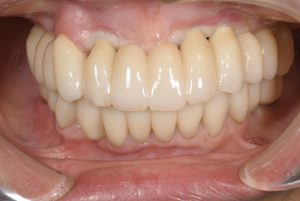

オールオン6(入れ歯からインプラント)

【オールオン4.オールオン6】

オールオン4.オールオン6(以下AO4.6)は上顎または下顎で歯が一本もない場合に行うインプラント治療です。

AO4ならインプラント4本、AO6ならインプラント6本の上に被せ物をつけます。

総入れ歯と異なり、サイズも普通の歯と同じになるため、喋りやすい、食事しやすい、見た目が良い、などの特徴があります。

③被せ物のセット

インプラント埋入から上顎では4ヶ月、下顎では3ヶ月後に被せ物を入れます。

期間、費用がかかる治療ですが、入れ歯から解放されて普通に食事、会話ができるようになる治療です。